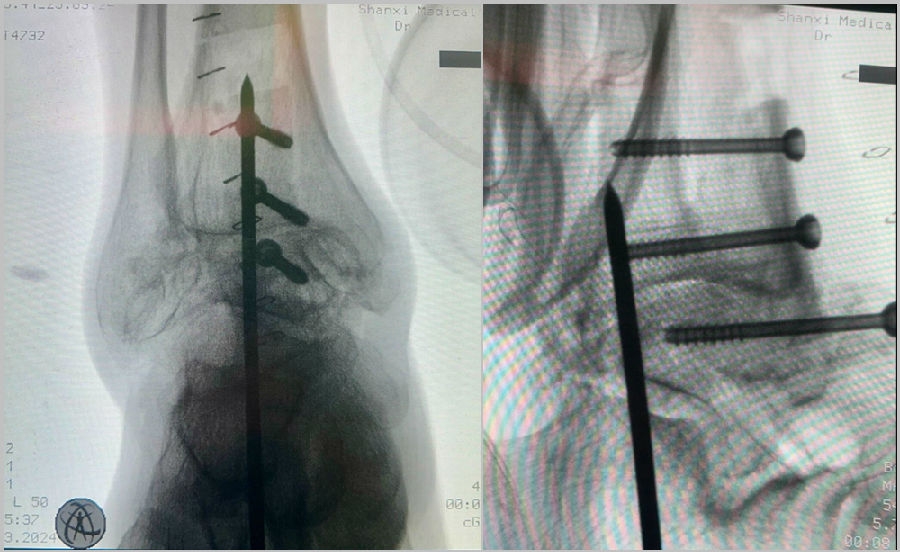

固定方法:

手术中资料

图23 手术后资料